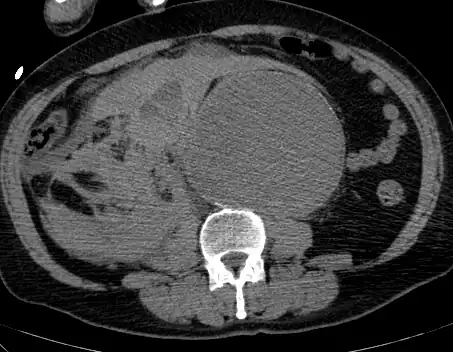

Abdominal

Abdominal aortic aneurysms (AAAs) are more common than their thoracic counterpart. One reason for this is that elastin, the principal load-bearing protein present in the wall of the aorta, is reduced in the abdominal aorta as compared to the thoracic aorta. Another is that the abdominal aorta does not possess vasa vasorum, the nutrient-supplying blood vessels within the wall of the aorta. Most AAA are true aneurysms that involve all three layers (tunica intima, tunica media and tunica adventitia). The prevalence of AAAs increases with age, with an average age of 65–70 at the time of diagnosis. AAAs have been attributed to atherosclerosis, though other factors are involved in their formation.[7]

The risk of rupture of an AAA is related to its diameter; once the aneurysm reaches about 5 cm, the yearly risk of rupture may exceed the risks of surgical repair for an average-risk patient. Rupture risk is also related to shape; so-called "fusiform" (long) aneurysms are considered less rupture-prone than "saccular" (shorter, bulbous) aneurysms, the latter having more wall tension in a particular location in the aneurysm wall.[9]

Before rupture, an AAA may present as a large, pulsatile mass above the umbilicus. A bruit may be heard from the turbulent flow in the aneurysm. Unfortunately, however, rupture may be the first hint of AAA. Once an aneurysm has ruptured, it presents with classic symptoms of abdominal pain which is severe, constant, and radiating to the back.[9]

The diagnosis of an abdominal aortic aneurysm can be confirmed by the use of ultrasound. Rupture may be indicated by the presence of free fluid in the abdomen. A contrast-enhanced abdominal CT scan is the best test to diagnose an AAA and guide treatment options.[10]